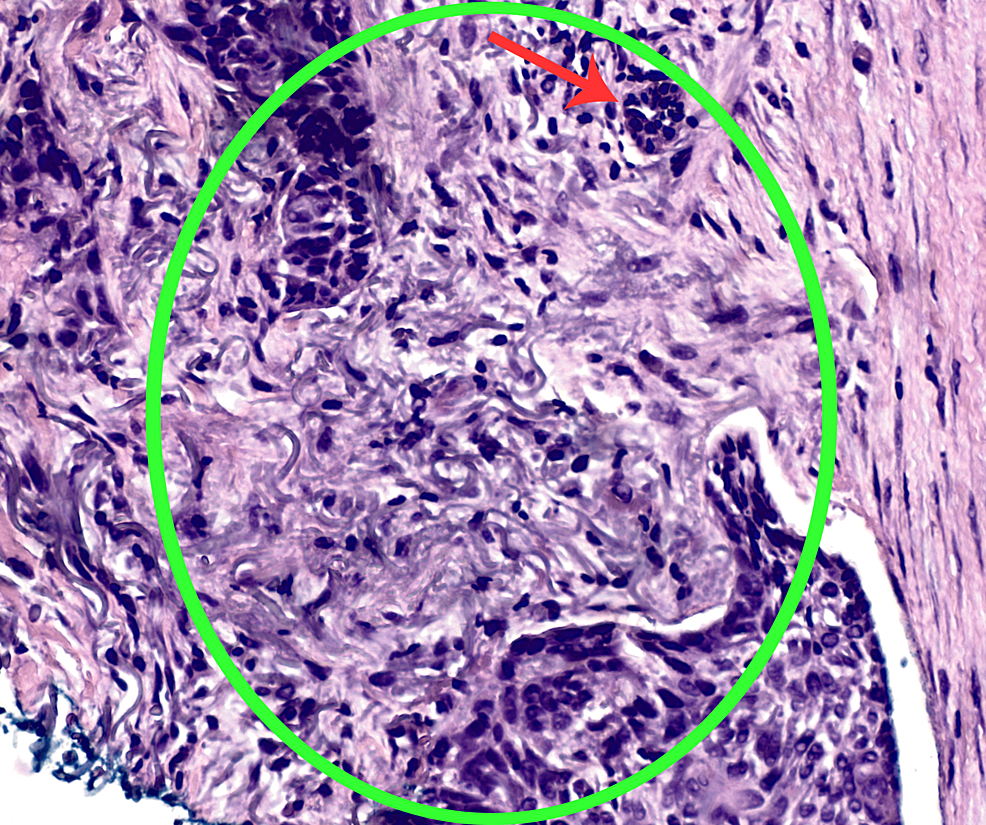

H&E stain of left lateral neck punch biopsy at 10x magnification H&E Punch Biopsy Bcc Your doctor uses a special instrument to take a punch biopsy. Punch biopsy is the preferred method of sampling for most inflammatory dermatoses because it allows the pathologist. Basal cell carcinoma (bcc) is the most common type of cancer in the world. The recommended biopsy techniques for bcc are punch biopsy, shave biopsy, and excisional biopsy. Occasionally a small punch. Punch Biopsy Bcc.